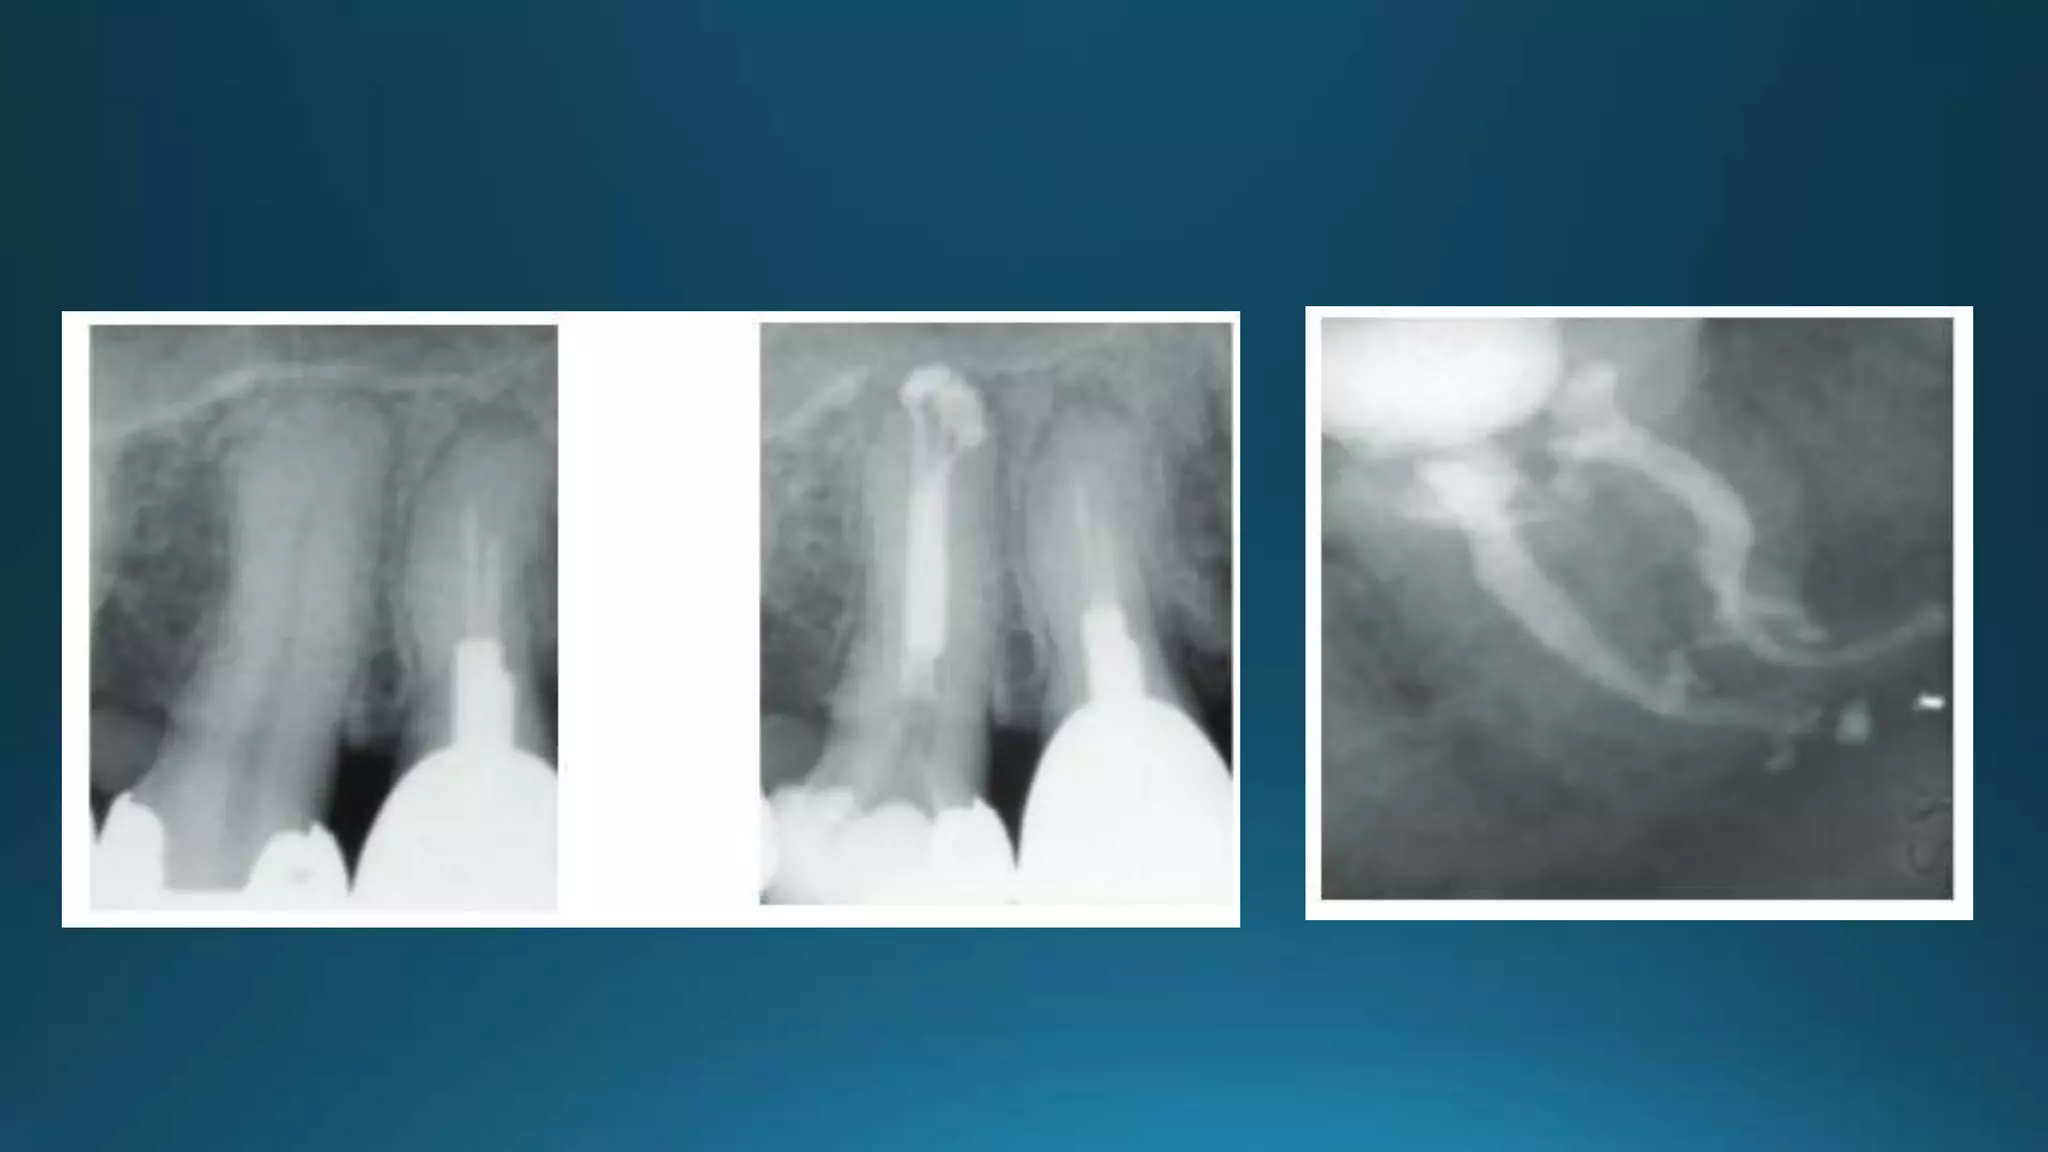

ACCESSORY CANAL

Accessory canals occur in three distinct patterns in the mandibular first molars.

A, In 13% a single furcation canal extends from the pulp chamber to the intraradicular region.

B, In 23% a lateral canal extends from the coronal third of a major root canal to the furcation region (80%

extend from the distal root canal).

C, About 10% have both lateral and furcation canals.

does not appear to be significant factor

granulation tissue

percentage of failures due to unfilled lateral canals is small